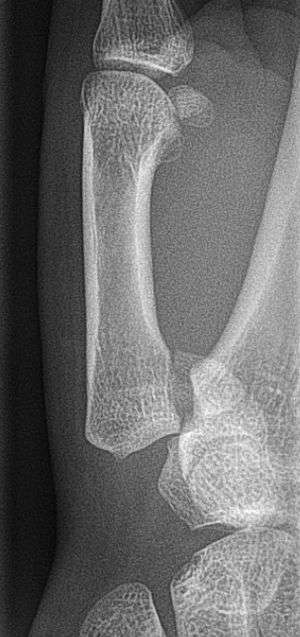

In the case of the Bennett fracture, the proximal metacarpal fragment remains attached to the anterior oblique ligament, which in turn is attached to the tubercle of the trapezium bone of the CMC joint. This ligamentous attachment ensures that the proximal fragment remains in its correct anatomical position.

The distal fragment of the first metacarpal bone possesses the majority of the articular surface of the first CMC joint. Unlike the proximal fracture fragment, strong ligaments and muscle tendons of the hand tend to pull this fragment out of its correct anatomical position.

- In the most minor cases of Bennett fracture, there may be only small avulsion fractures, relatively little joint instability, and minimal subluxation of the CMC joint (less than 1 mm). In such cases, closed reduction followed by immobilization in a thumb spica cast and serial radiography may be all that is required for effective treatment.[4]